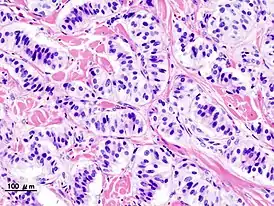

Гистологическая картина

- Патогистология

.JPG.webp)

Панкреатическая инсулинома .JPG.webp)